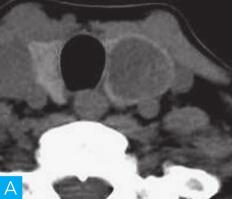

甲状腺CT检查:CT检查设备为256层iCT,病人采取仰卧位,扫描范围自外耳道平面至下颌角以下,常规扫描层厚为0.9mm、层间隔0.9mm,电压120kV,管电流280mA,矩阵512×512;经右肘静脉团注法增强扫描,碘海醇80ml,流速4ml/s,动脉期25秒扫描,静脉期60秒扫描。见图1。

图1 甲状腺CT

A、B.甲状腺CT横断面平扫;C~H.甲状腺CT横断面增强

答案A 解析:甲状腺左叶病变边界清楚,形态较规则,密度不均匀,部分为实性改变,部分为囊性灶,其内可见斑点状粗大钙化灶,气管及食管向右推移,左侧颈总动脉向左后推移,胸锁乳突肌向左前推移。根据表现病变不是单纯囊性病变。

CT平扫可见甲状腺左叶圆形以低密度为主病灶,大小为8.0cm×6.5cm,边界清晰,边缘尚光整,其内密度不均匀,低密度区CT值18HU,部分密度稍高,并可见斑点状粗大钙化影;CT增强后,甲状腺左叶病变呈不均匀渐进性强化,结节状改变,动脉期强化区CT值99HU,静脉期CT值85HU,且强化范围增大,提示该病变的血供较为丰富,应该考虑肿瘤样病变,结节性甲状腺肿可能性大。

本病例CT扫描发现起源于甲状腺较为容易,但要观察病变是囊性、实质性或囊实性及其供血,CT增强扫描十分必要,易于显示囊实性病变及其供血情况,其结节状改变更加显著,有助于判定病灶的血液供应情况。本病例基本征象为类圆形、边缘清晰、内粗大钙化、结节状强化之肿块。